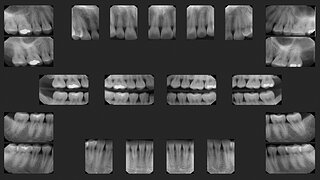

牙科放射線學實驗